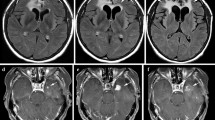

Definite, and to a certain extent, progressive macrovascular cerebral arteriopathy (vessel narrowing and irregularity) was seen in five (22%) patients with coexistent parenchymal ischemic changes in some cases (Figs. 3 and 4).

In a few cases, there were territorial arterial infarcts, with other potential causes of infarction having been excluded. We confirmed necrosis on biopsy in one patient. The case was biopsied as there was discrepancy among the clinical team if the lesions represented true progression or not, with indeterminate results on advanced imaging (MR perfusion); being a posterior fossa lesion, MR spectroscopy also was inconclusive because of technical limitations.

Example of CA and radionecrosis type changes. Self-resolving ischemic changes in patient with posterior fossa anaplastic ependymoma. Axial FLAIR (a, b), axial DWI (c), and axial post-contrast T1W (d) sequences showing progressive abnormal signal change, diffusion restriction, and enhancement, respectively, in pons and R MCP (biopsy confirmed necrotic tissue) (Fig. 5). Axial T2W and DWI sequences (e, f) showing resolution of changes after 1 year